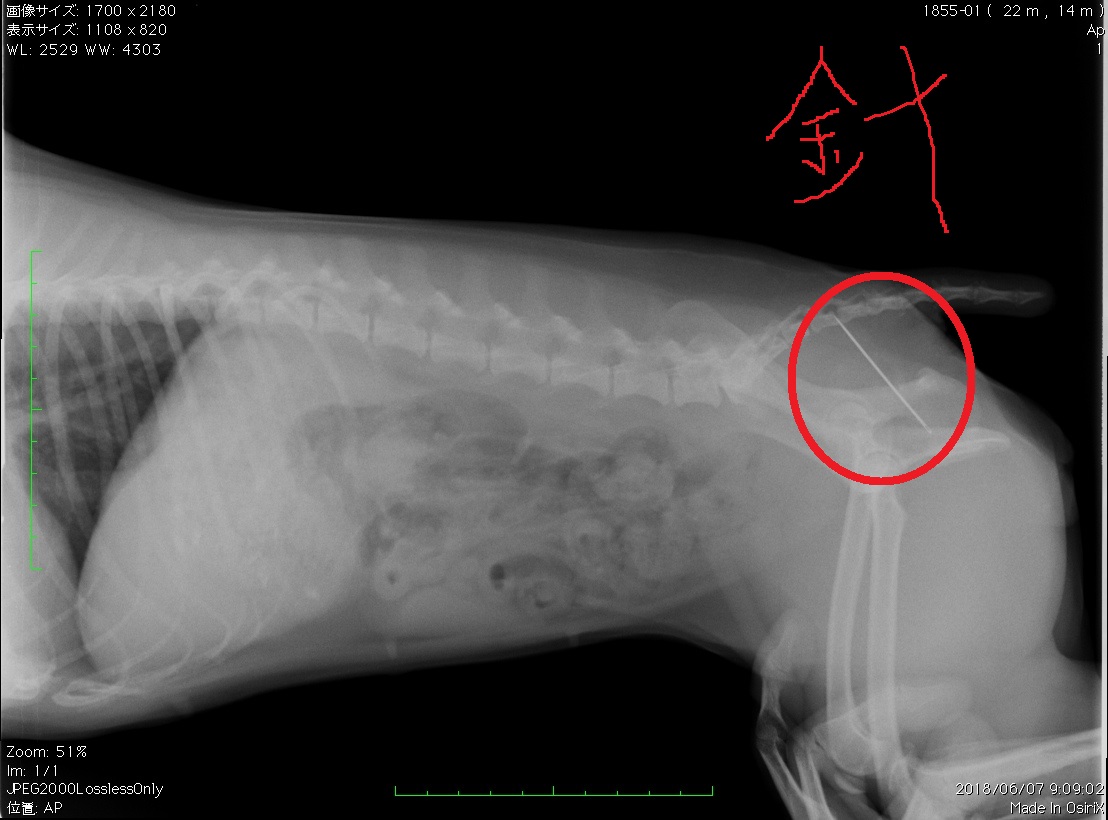

ミニチュア・ピンシャー  メス  1歳3か月

いつ飲み込んだかわからないけど、おしりから針が出てきたといって来院されました。

縫い針を飲み込んでしまったようです。犬の口は人間の手と同じです。興味をもったものは口でくわえて、遊んだり、噛んだりします。その延長で、事故的に飲み込んでしまったのかもしれません。

赤丸で囲んだ中の白く細長いものが針です。

鎮静麻酔をかけておしりから針を取り除きました。

元気いっぱいで、食欲もありました。下痢、嘔吐などの症状もありません。これだけ長い針が腸を傷つけたり、貫通せずに肛門まで出てくるケースは少ないと思います。大事にならなくてよかったです。